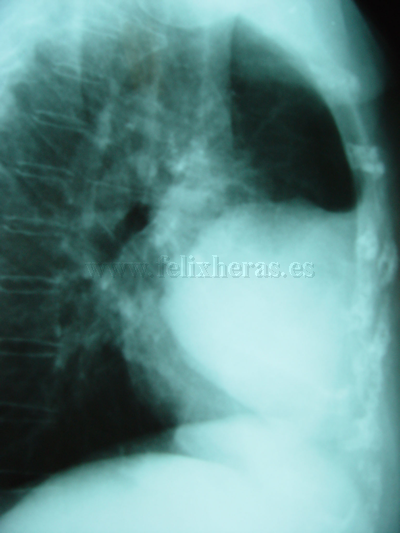

Mesotelioma fibroso pleural